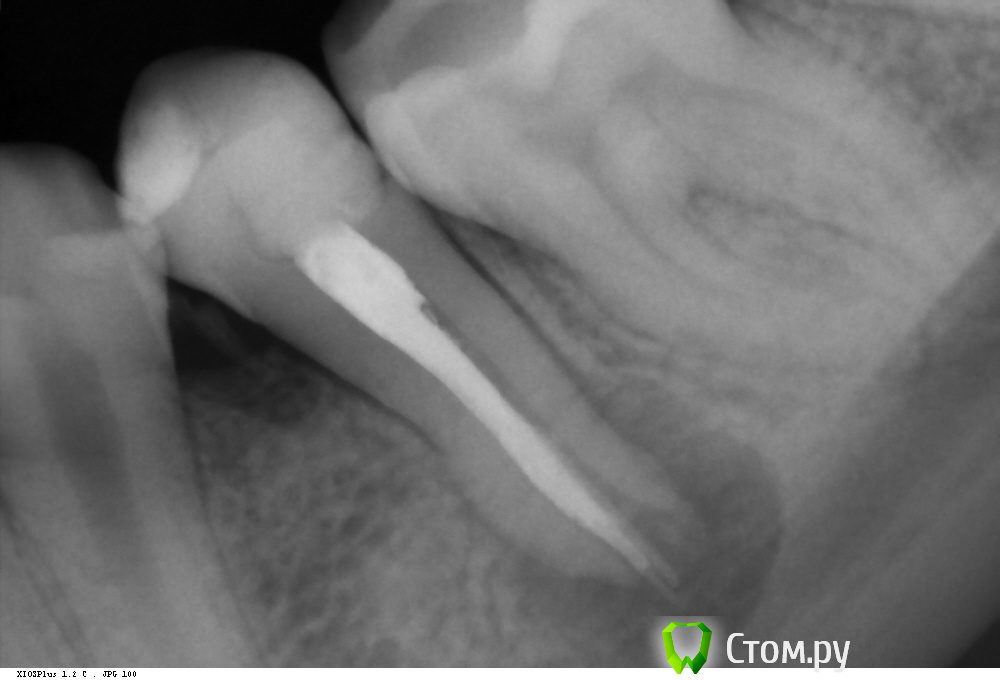

Shaid Опубликовано 9 марта, 2014 Поделиться Опубликовано 9 марта, 2014 (изменено) Пациентка, 14 лет обратилась с постоянной ноющей болью в 35 зубе, болями при накусывании.Объективно: пломба на жевательной и дистально-контактной пов-ти. В канале гуттаперча. Перкуссия +.Распломбировал гутту(оставил часть в апексе, потому что не смог вытащить, а время приема заканчивалось), промыл(кровило), оставил кальций.Какова дальнейшая тактика в данном случае?Стоит ли ждать формирования апекса(вести через кальций) или на следующее посещение закрыть мта? Нужна ли РВК? Кому в апексе видится латераль? Изменено 9 марта, 2014 пользователем Shaid Ссылка на комментарий

Каплан Опубликовано 9 марта, 2014 Поделиться Опубликовано 9 марта, 2014 (изменено) больше похожу на глубокий сплит.. как на 5ке на моем снимкеhttp://imagizer.imageshack.us/v2/xq90/28/2xk1.jpgпричем в твоей ситации первый доктор пропустил этот сплит можно конечно вычистить гутту и постараться вытянуть зуб через реваскуляризацию... но не уверен что получится при перелечивании... она и так-то не очень успешная... на апексогенез особо не расчитывал бы.скорее всего провел бы на кальций и апикальная пробка из мта. хотя вполне можно и гуттаперчу, только откалибровать. Изменено 9 марта, 2014 пользователем Каплан Ссылка на комментарий

Shaid Опубликовано 10 марта, 2014 Автор Поделиться Опубликовано 10 марта, 2014 Это довольно сложный зуб и я бы донес до родителей информацию об этом.Донес. но послать желательно адресно к тому, кто сможет это сделать.Имеете ввиду микроскописта? После полного удаления гуттаперчи есть снимок?Полного удаления гуттаперчи не было) в апексе осталось. Есть только такой снимок(с кальцием), хотя ничего информативного, на мой взгляд, он не несет. Ссылка на комментарий

Kolchanov Опубликовано 10 марта, 2014 Поделиться Опубликовано 10 марта, 2014 Клади не контрастный гидроксид, если хочешь посмотреть сколько старого материала осталось. Кальсепт, например.Даже когда на рентгенограмме все пучком, заглянешь с оптикой в канал и удивишься, сколько там еще осталось по стенкам. Микроскоп бы хорошо. Не будешь же гуттаперчу в апексе в Триоксидент вмуровывать.Какой там размерчик получился? По снимку кажется, что и 140 пролетит. 1 Ссылка на комментарий

Shaid Опубликовано 10 марта, 2014 Автор Поделиться Опубликовано 10 марта, 2014 Да у нас кроме Метапасты/Метапекса нет паст. Я и без оптики(хотя с удовольствием бы одел) вижу, сколько там материала осталось) В апексе гуттаперча туда-сюда болтается, но не выходит. Пробовал и пульпэкстрактором подцеплять, и двумя пульпэкстракторами, и H-файлом, и раскаленными H-файлом. Как еще можно ухитриться достать? ) Ссылка на комментарий